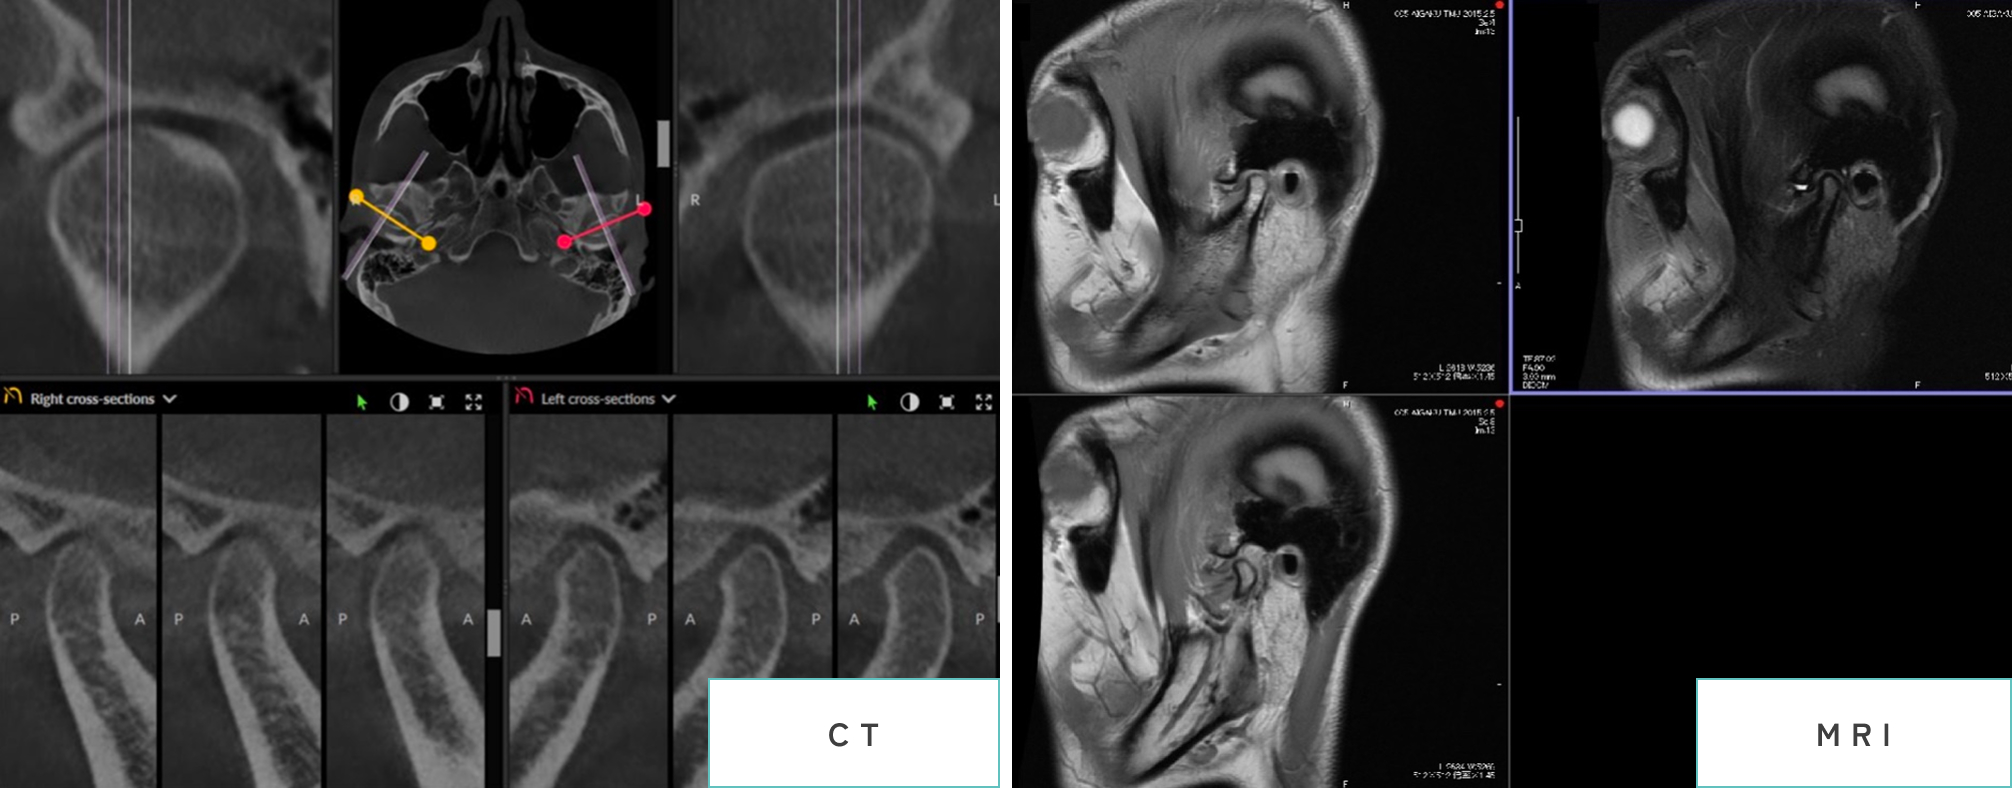

当院では最先端のCTを用意しており、より詳細な顎関節の状態評価が可能です。また、必要に応じてMRIが必要な症例については近隣の総合病院と連携をとり、撮像を行っております。